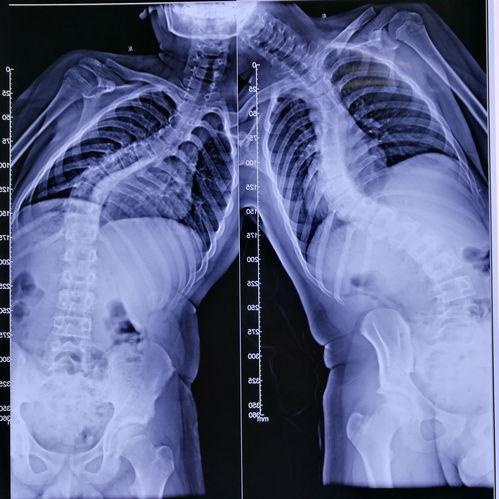

首先,让我们来了解一下脊柱侧弯。脊柱侧弯是一种常见的脊柱畸形,主要表现为脊柱向一侧弯曲。这种疾病不仅影响患者的体型,还可能引发疼痛、呼吸不畅等一系列问题。据统计,全球约有3%的人患有脊柱侧弯。

手术开始了,医生首先在女孩的背部切开一个小口,然后插入一根细长的金属棒。这根金属棒将贯穿整个脊柱,起到支撑和矫正的作用。接下来,医生在金属棒的两侧分别安装了两个金属钩,将它们固定在女孩的脊椎骨上。

随后,医生开始调整金属钩的位置,使脊柱恢复到正常状态。这一过程需要精确的操作,因为任何一点偏差都可能导致手术失败。经过一番努力,医生终于将脊柱矫正到理想的位置。

接下来,医生将金属棒与金属钩连接起来,形成一个稳定的支架。医生在手术切口处缝合,手术宣告成功。